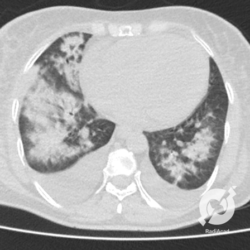

Consolidações alveolares e opacidades em vidro fosco peri-hilares, com espessamento septal e derrame pleural bilateral. Edema agudo de pulmão.